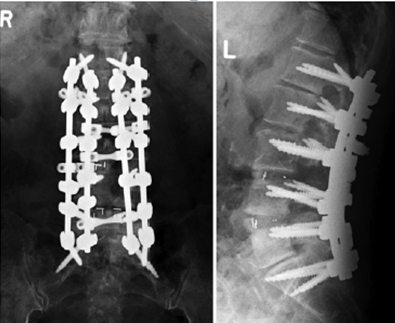

图12 CBT+TT+多棒固定

CBT+TT+多棒固定

从融合节段向活动节段未行过渡性手术,导致局部应力分布不均,局部应力过于集中,也是交界性问题的危险因素之一。

长节段固定时,融合区和活动区应适当行过渡性手术,可降低PJK发生的风险。

图13 长节段全椎弓根螺钉固定,局部应力过于集中